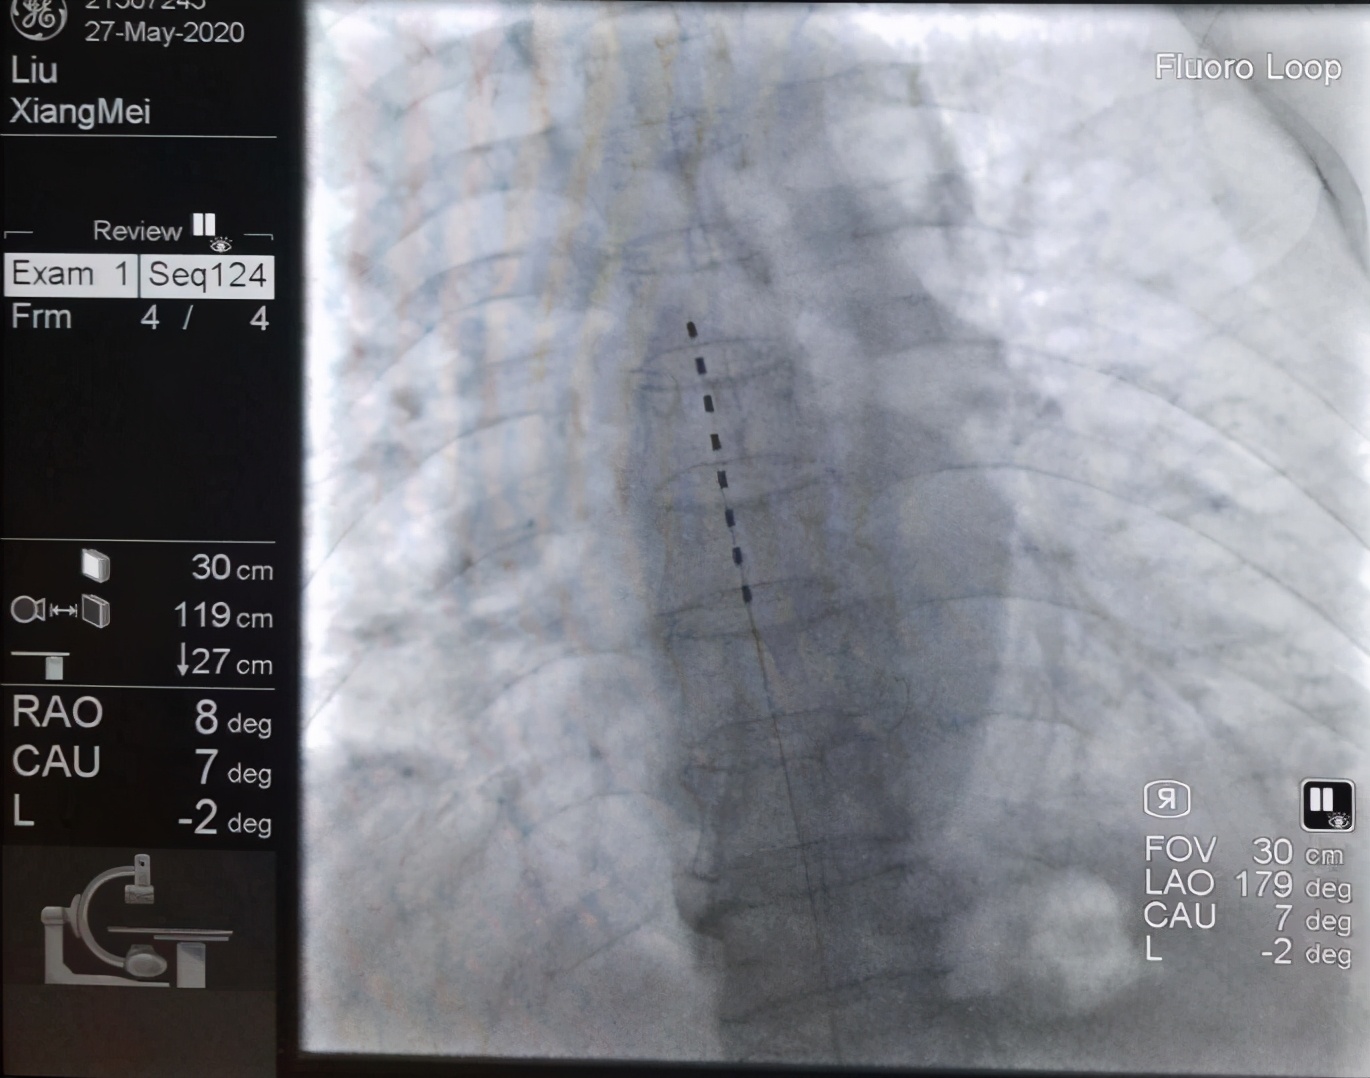

近日,太原市中心医院疼痛科收治了一位62岁的患者何阿姨。两年前,何阿姨因脊柱后凸畸形、腰椎间盘突出症在当地医院行脊柱后凸畸形矫正术(T12-L1、S1椎弓根内固定)。

术中,主治医生为何阿姨行L1、L2、L3S神经根脉冲调控治疗,完全复制出疼痛症状。

由于何阿姨之前做过开放手术,腰部软组织瘢痕增生明显,正常结构紊乱,给穿刺过程带来极大的困难。